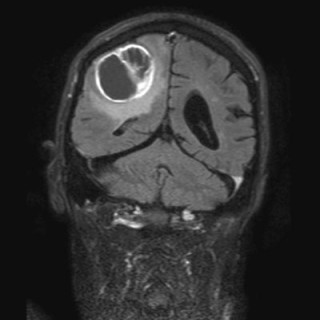

Sentrale venekatetre brukes rutinemessig i pasientbehandlingen ved norske sykehus. Den sentralvenøse tilgangen oppnås gjennom punksjon av v. jugularis interna, v. subclavia eller v. femoralis. Komplikasjoner knyttet til bruken ses både i forbindelse med selve innleggingen av kateteret, når kateteret er på plass og i bruk og når det skal fjernes. Komplikasjoner knyttet til innlegging av et sentralvenøst kateter er punksjon av nærliggende arterie, pneumothorax, arytmier, skade av plexus brachialis, skade på ductus thoracicus, luftembolisering og feilposisjonering av kateteret (1, 2)...